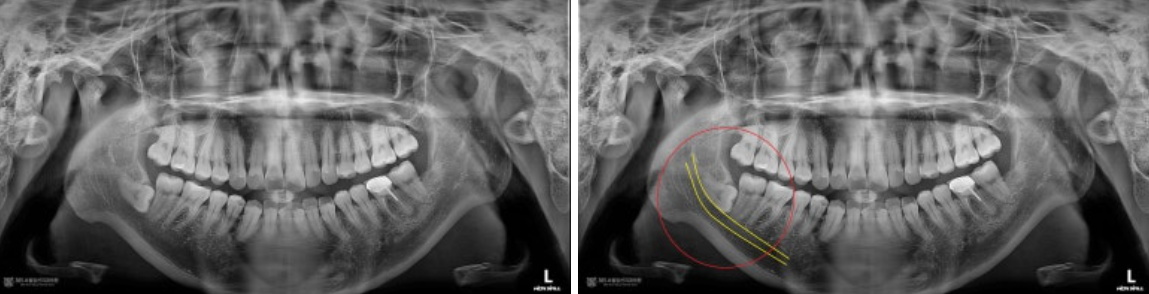

촬영일시 : 2024.09.06. 사진상에서 좌측(구강내 우측) 아래쪽에 아주 깊게 매복된 사랑니가 관찰됩니다. 노란색으로 표시된 신경관과 수평으로 완전히 접하고 있는 모습을 볼 수 있으며, 발치 난이도가 매우 높아 보입니다. 신경손상이 없이 안전하게 발치해야겠습니다.